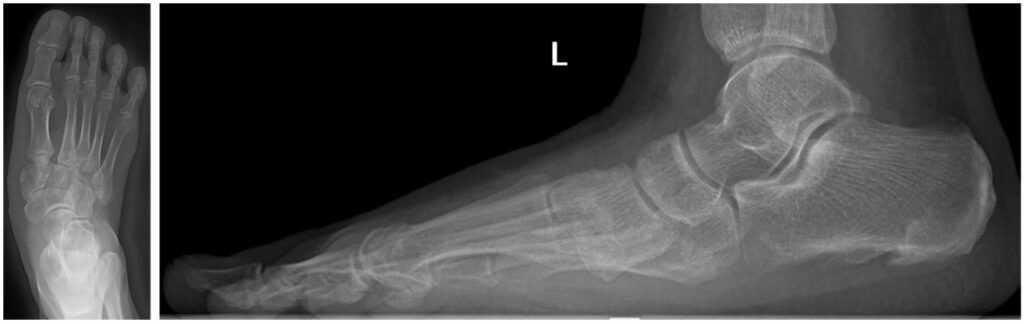

Больше года молодой житель Новосибирска Руслан Ермолаев испытывал сильную боль при ходьбе и даже в положении стоя. В мае 2024 года он получил травму при падении — обратился к врачам по месту жительства и был отправлен на амбулаторное лечение.

Однако с течением времени появились боли и деформация в области среднего отдела левой стопы. Руслан не мог полностью наступать на ногу и, как отмечает сам, «жил на обезболивающих», чтобы продолжать работать.

Перед специалистами травматолого-ортопедического отделения №6 Новосибирского НИИТО им. Я.Л. Цивьяна Минздрава России стояла задача коррекции сложной посттравматической деформации. Исходная травма привела к стойкому смещению костных фрагментов, что выражалось в грубой деформации стопы, болевом синдроме и нарушении её опорной функции.